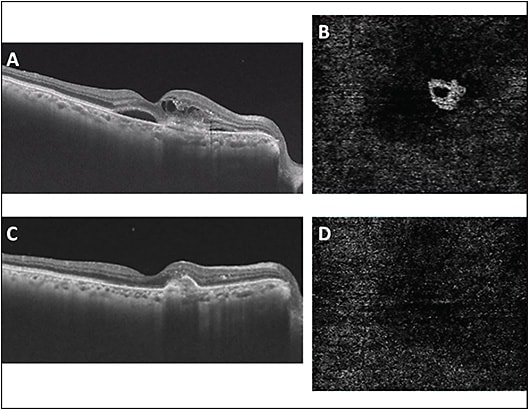

Age-related macular degeneration (AMD) is characterized by the presence of drusen, which can progress to geographic atrophy (GA) and/or choroidal neovascular membrane (CNVM) in advanced stages.14 Loss of CC in turn leads to the loss of retinal pigment epithelium (RPE) and photoreceptors. Increased areas of CC flow impairment are seen in eyes with intermediate AMD, which are present beneath or near the areas of the underlying drusen.15 Eyes with reticular pseudodrusen show similar findings of CC nonperfusion areas, which have been shown to correlate with poor visual acuity.5 OCTA in geographic atrophy (GA) (Figure 1) shows areas of CC loss with reduced vascular density that extend beyond the areas of GA.16

Early CNVM identification and treatment response assessment can be aided by OCTA. Nonexudative CNVM is a distinct entity characterized by the absence of intraretinal or subretinal fluid.17 In these eyes, progression to frank CNVM is more common than progression to intermediate AMD, and therefore this risk warrants closer follow-up.18 Exudative CNVM can be defined qualitatively (morphologic description, type 1, 2, or 3) and quantitatively (area, vessel density) using OCTA.8,19,20 The treatment response can be measured in terms of reduction of CNVM size.9 Representative images are shown in Figure 2. However, complete disappearance of CNVM is rarely seen, and thus OCTA must be analyzed along with the structural OCT to determine future treatment plans.